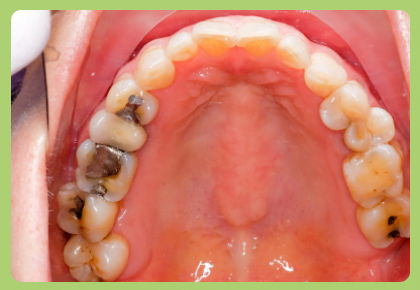

small shallow cavities can be filled with dental cements which prevent further deepening of the decay and stops spreading decay to the next tooth